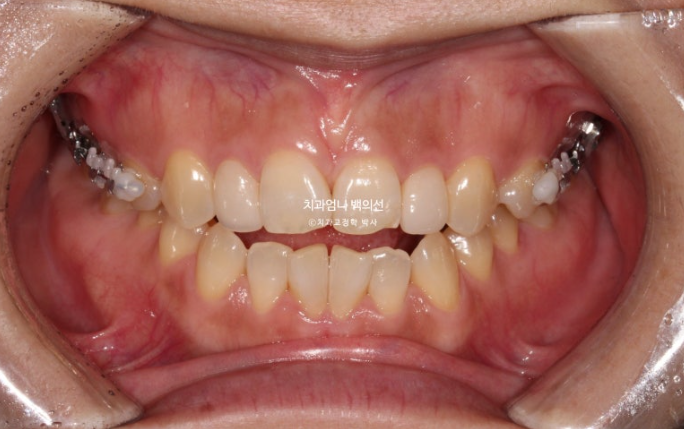

24.10

치료시작으로부터 1년 5개월 후 모습입니다. 먼저 위 장치 다 떼고 피팅준비를 합니다.

파란 화살표 측절치는 환자분이 오래전 했던 왜소치 라미네이트입니다.

이 라미네이트도 제거 후 재제작 하기로 합니다.